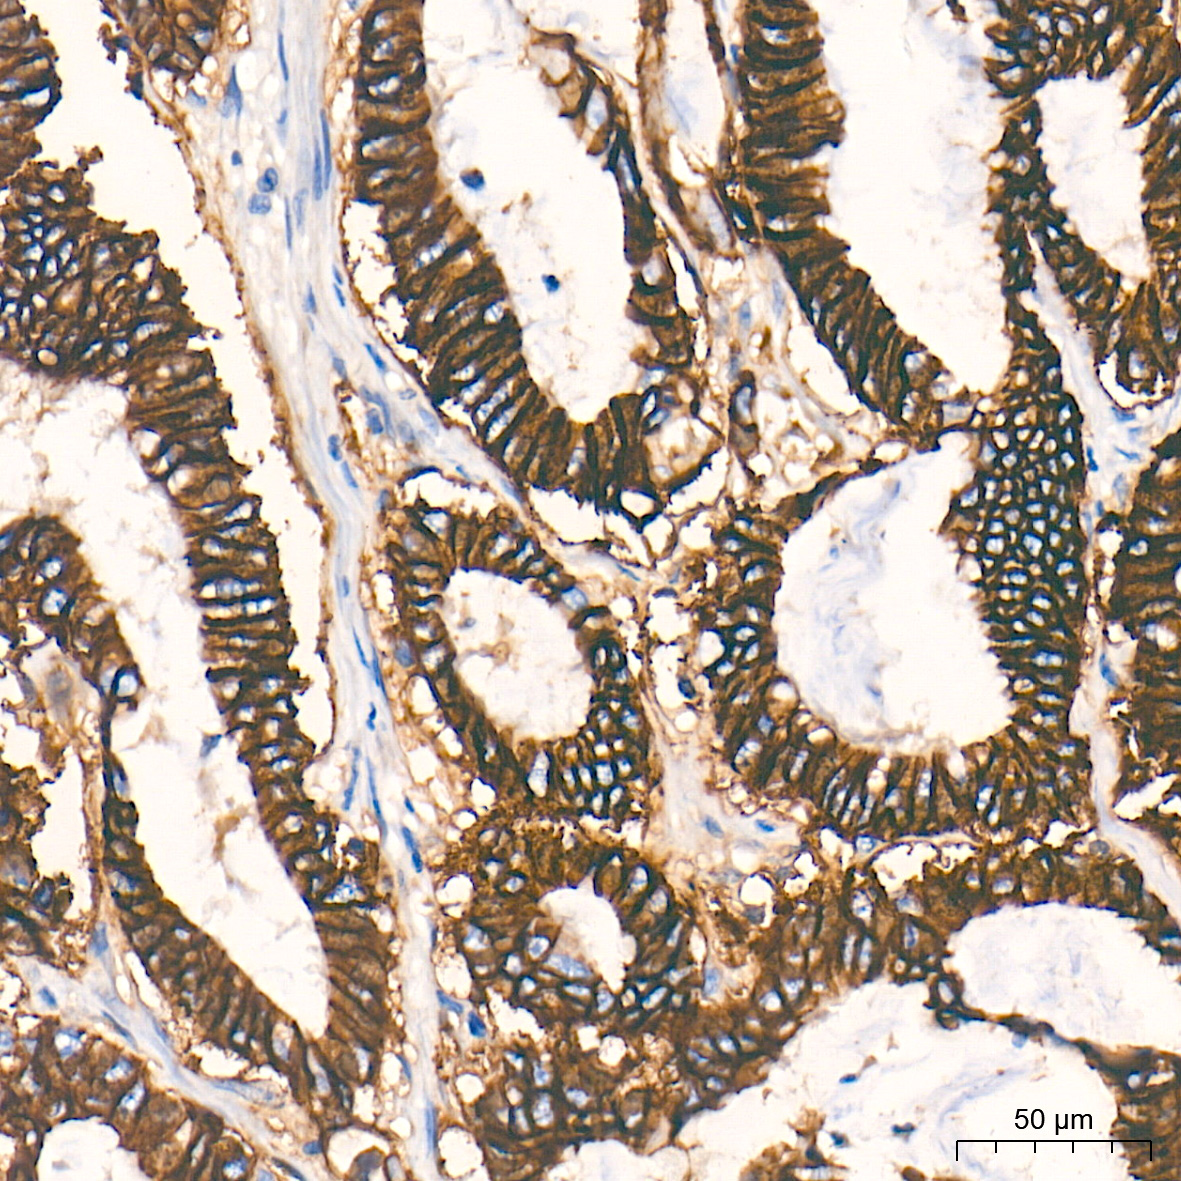

细胞骨架(Cytoskeleton)由微管(Microtubule)、微丝(Microfilament)及中间纤维(Intermediate filament)组成,是细胞器互作和细胞间交流的结构基础,在胚胎发育和机体稳态平衡的建立和维持等生理过程中发挥重要作用。微管主要由α及β微管蛋白组成,微管数量的减少是细胞恶性转化的重要标志。微丝主要由肌动蛋白(Actin)构成和肌球蛋白(Myosin)一起发挥作用,在肿瘤细胞内原有的微丝束明显减少甚至消失,常出现肌动蛋白凝聚小体。中间纤维常由波形蛋白(Vimentin)、角蛋白(Keratin)、结蛋白、神经元纤维、神经胶质纤维构成,在肿瘤中瘤细胞仍能基本保持其起源细胞的中间纤维类型,这有助于确定肿瘤组织的起源。细胞骨架信号会受到包括Rho家族以及它们的下游蛋白激酶效应器Rho激酶(ROCK)和p21活化激酶(PAK)的调控。